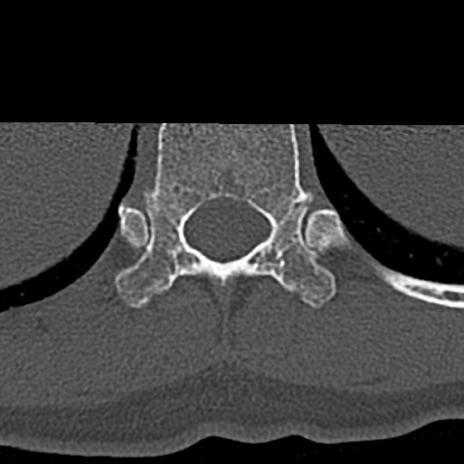

腰椎CT

横断像と矢状断像